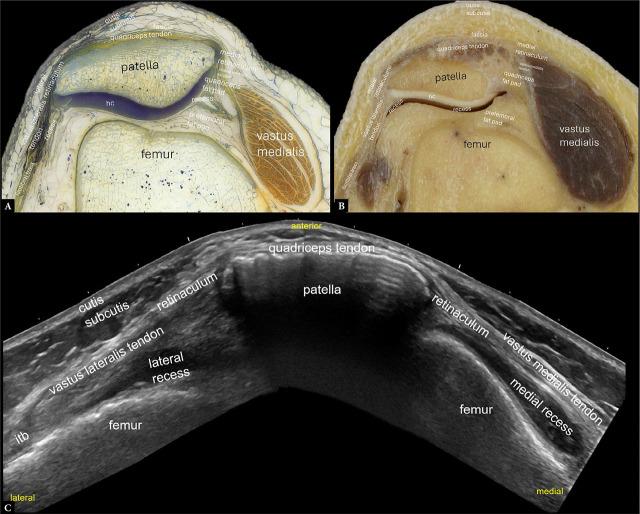

Enhancing knee imaging via histology and anatomy-driven high-resolution musculoskeletal ultrasound.

Normal ultrasound images were obtained from a healthy subject, and corresponding images of human anatomy and histology were acquired from body donors.

Several high-resolution ultrasound, anatomical, and histological images were created to illustrate and comprehensively describe the basic standard scans in compliance with international standards. This atlas summarizes a selection of typical normal findings.

This overview explains the normal anatomy of the knee as seen by ultrasonography. High-resolution knee musculoskeletal ultrasonography aims to provide an accurate structural evaluation, which requires comprehensive knowledge of sonoanatomy. When used appropriately, contemporary high-resolution musculoskeletal ultrasonography enhances knee imaging by connecting anatomical cross-sections and intricate histology to specific anatomical features.